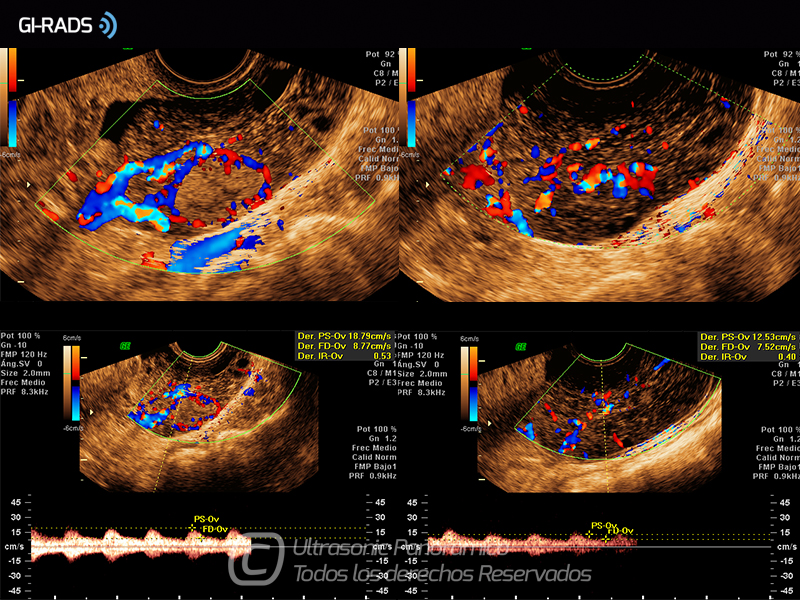

Cáncer Anexial – Flujo Abundante

• Cáncer Anexial – Flujo Abundante